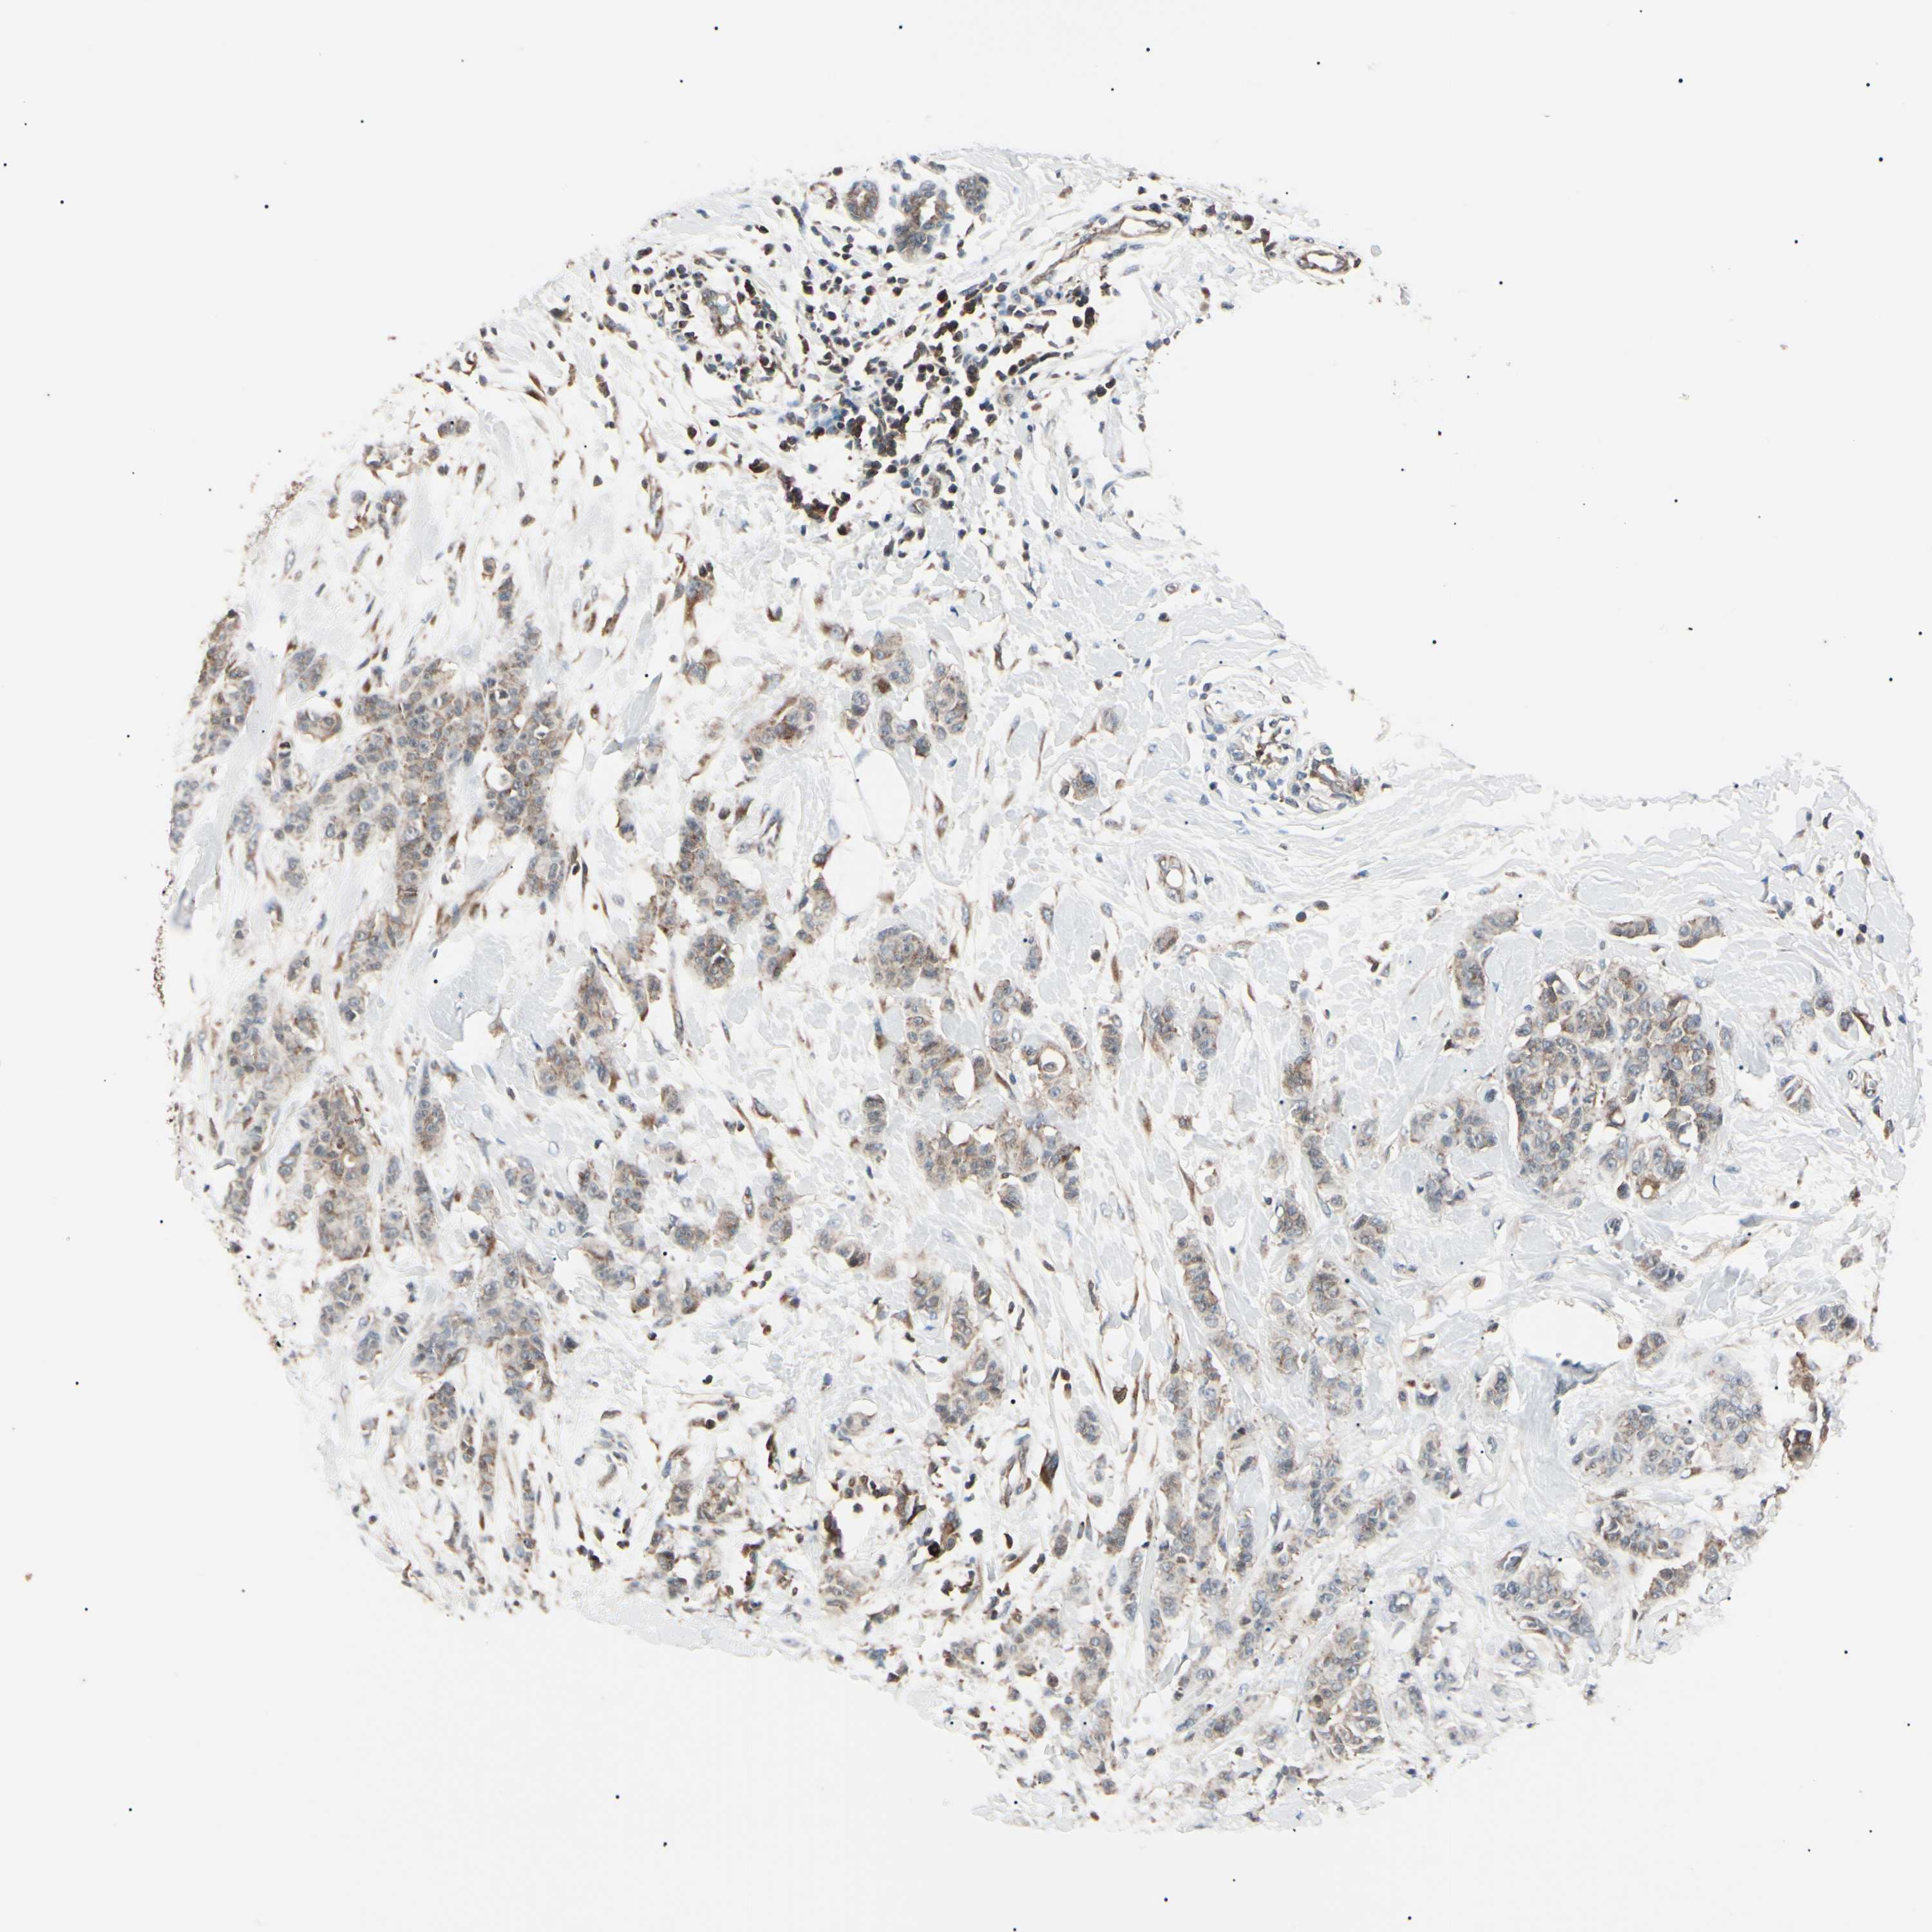

BRCA TCGA BRCA VALIDATION PROTEIN EXPRESSION